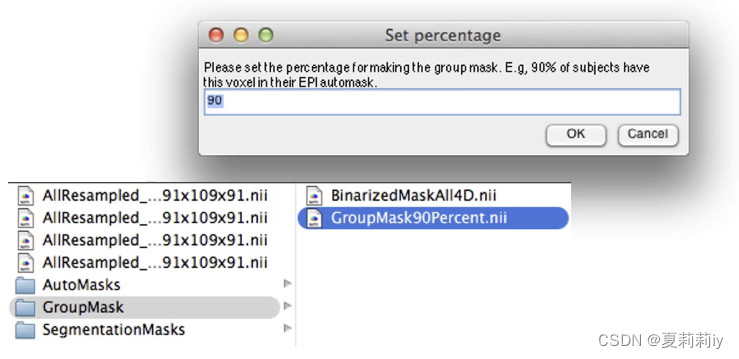

(6)Generate Group Masks

①wAutoMask是MI空间,且根据它可以生成GroupMask

②可以在这个文件中输入值,此例为要求90%的被试都cover这个voxel才进入GroupMask(即进入统计分析)